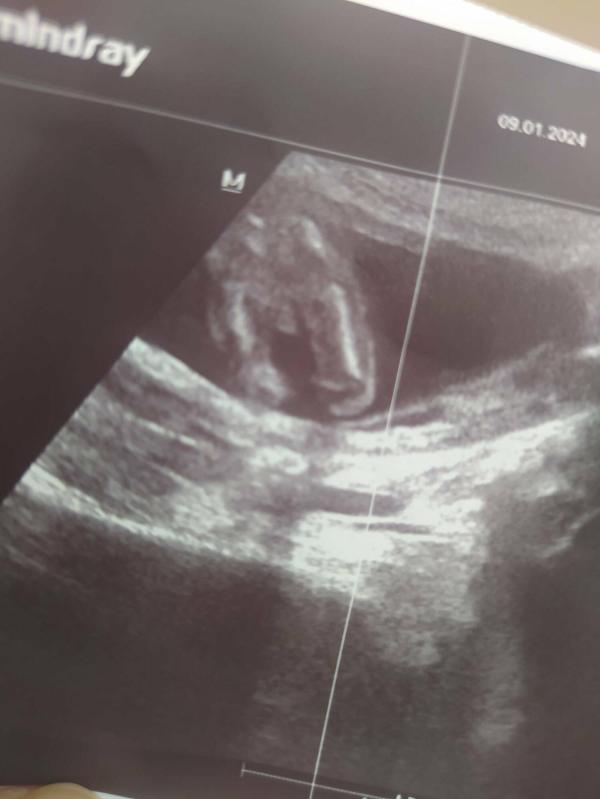

Кто это?

Угадаете кто?😂

Мальчик

Там прям видны причиндалы